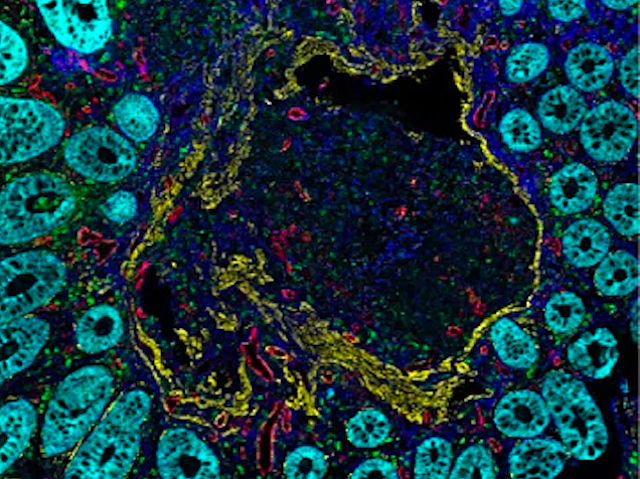

Resident Upheaval

Using imaging mass cytometry and single-cell RNA sequencing to analyse the cellular composition and topology of the tissue changes with ulcerative colitis – inflammatory macrophages replace resident macrophages